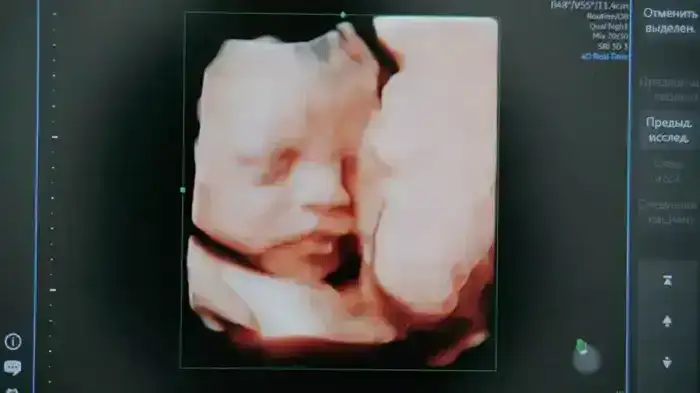

В Карагандинской области начинается реализация пилотного проекта, направленного на раннее выявление spina bifida — редкой патологии развития позвоночника и спинного мозга у плода. Инициаторами проекта выступили Yandex Qazaqstan и региональное управление здравоохранения, при поддержке акимата области. Основой разработки является система искусственного интеллекта, созданная для анализа ультразвуковых снимков, полученных на 11—14 неделе беременности.

Система будет использовать искусственный интеллект для анализа результатов УЗИ беременных. Важно отметить, что будут обрабатываться только изображения без использования персональных данных. Облачные технологии Yandex Cloud обеспечат хранение и обработку данных, а также обучение нейросетей.